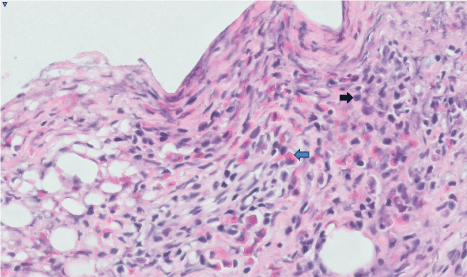

Figure 3: Histology revealing eosinophilia [blue arrow] and plasmacytoid lymphocytes [black arrow].